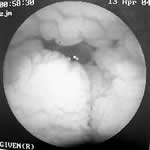

患者男性,48岁,因“双下肢水肿1年、间断腹胀7个月”入院。

患者1年来无明显诱因出现双下肢轻度水肿,下午、夜间较重,无尿量减少和颜面部水肿。7个月来进食肉类后感腹胀不适,有时发热达38℃,伴恶心、呕吐胃内容物,或腹泻水样便;禁食1~2天后好转,无腹痛,2个月内发作4~6次。5个月前患者出现饥饿性上腹痛2周,在外院诊断为“十二指肠溃疡”,按溃疡病治疗无明显缓解。1个月来双下肢水肿加重,伴明显乏力。外院查血WBC 3.2×109/L,淋巴细胞48%,血红蛋白Hb111 g/L,血小板PLT183×109/L ......